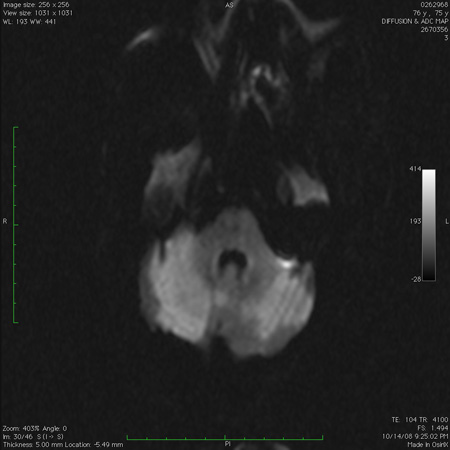

Infarto medular dorsolateral junto com infartos dispersos no cerebelo, observado na imagem de ressonância nuclear magnética ponderada na sequência de difusão

Do acervo de Dr. S. H. Subramony; usado com permissão